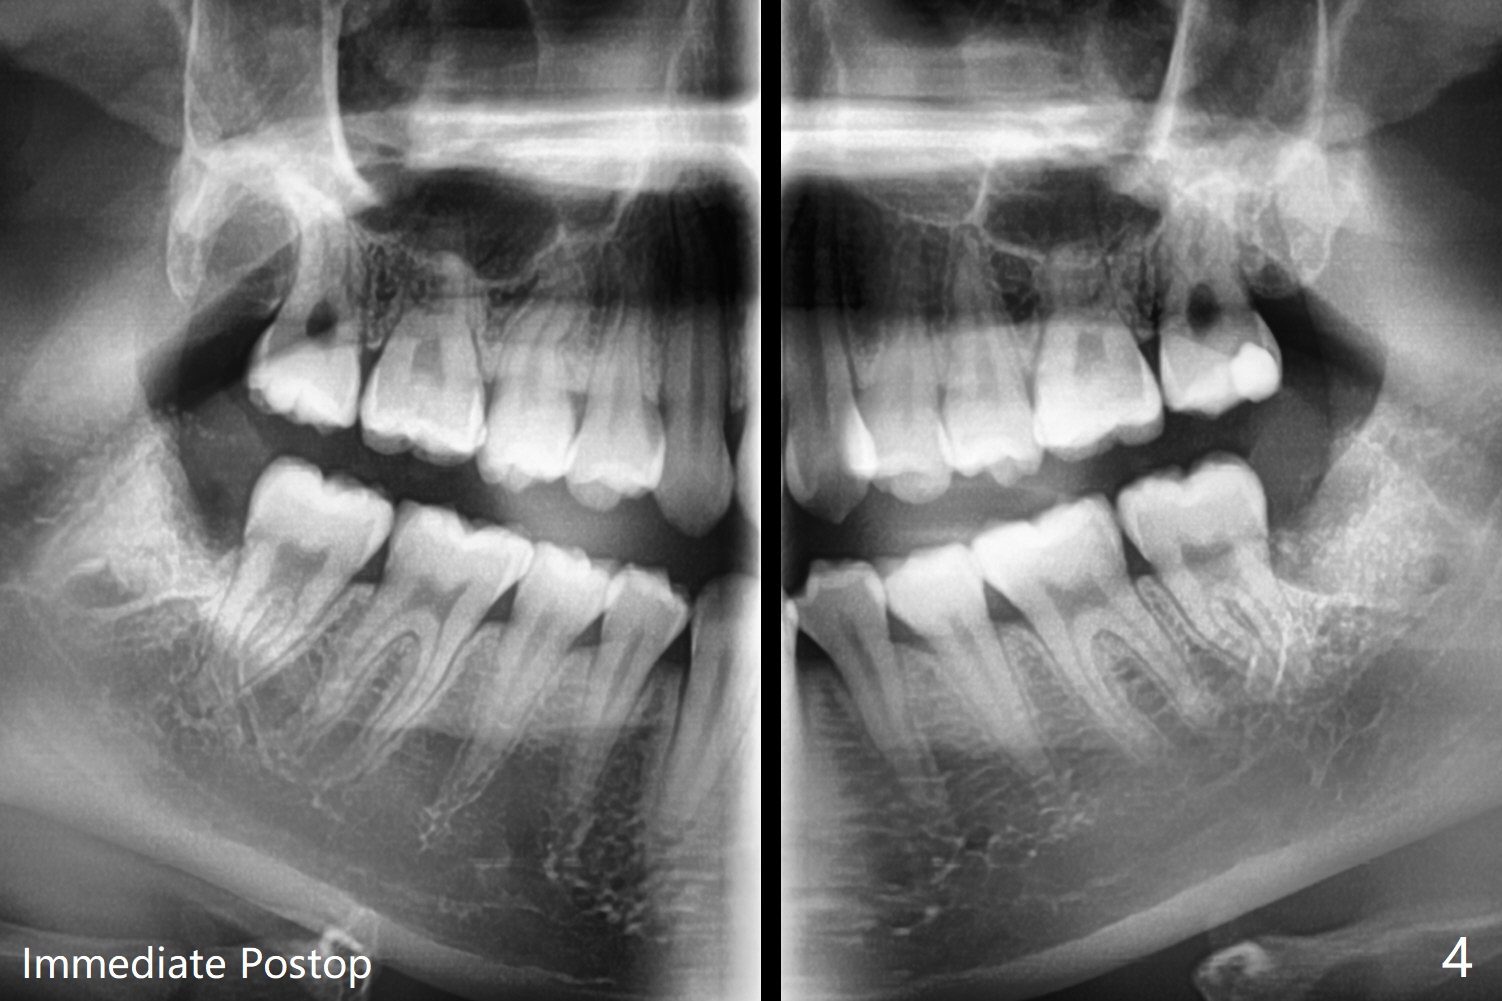

15岁女孩外斜嵴好像小三角形,骨质密度低(图一),18岁时三角形变大,密度增高(图二)。术前拍摄小范围CT,术中切开后,拍摄照片显示外斜嵴,随着颊侧去骨,嵴被破坏(拍照)。

由于临床忙,没有术前拍摄CT,术中发现外斜嵴两侧都不明显(女孩原因?),拔除两侧都需要颊侧去骨。由于左侧智齿颊侧阻生(图三:*),拔除后两侧都放置骨水泥(Bond Apatite,图四:A)促进骨修复,口腔卫生欠缺,可能容易形成牙周炎。